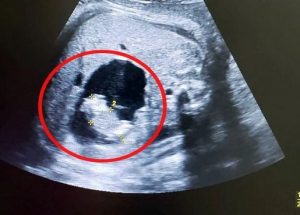

Το παγκόσμιο ρεκόρ κρατά η γέννηση διδύμων με 87 ημέρες διαφορά που σημειώθηκε το 2012, στη συγκεκριμένη περίπτωση, όμως, δεν είναι μόνο η ημερομηνία των γενεθλίων που χωρίζει αυτά τα δύο δίδυμα, αλλά και το γεγονός ότι κυοφορήθηκαν σε δύο ξεχωριστές μήτρες.

Όπως έγινε γνωστό, η μητέρα τους είχε «δίδελφυ μήτρα».

Πρόκειται για μια πάθηση που επηρεάζει μία στις 2.000 γυναίκες και περιγράφεται ως ύπαρξη δύο μητρών στο σώμα της γυναίκας.

Αντί δηλαδή να έχει σχήμα ισοσκελούς τριγώνου, έχει σχήμα σφεντόνας, χωρίζοντας έτσι στα δύο την κοιλότητα του ενδομητρίου.

Ωστόσο, οι πιθανότητες μιας εγκυμοσύνης όπως αυτή της Lilliya Konovalova, όπου κάθε έμβρυο αναπτύσσεται στη δική του ξεχωριστή μήτρα, είναι μόνο μία στα 50 εκατομμύρια.